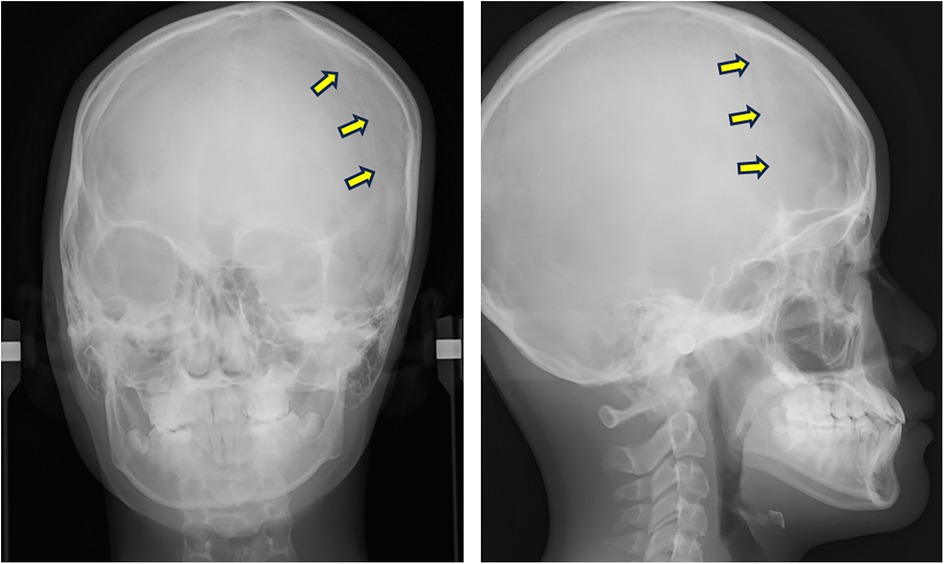

CT data of the skull were acquired using a helical CT scanner (Somatom Emotion 6; Siemens, Erlangen, Germany), and Digital Imaging and Communications in Medicine (DICOM) data were reconstructed using 3D imaging software (Dolphin 3D Image Software; GC Ortholy, Tokyo, Japan). Dental cast data were obtained using a 3D surface scanning system (Rexcan DS2; Solusnix, Seoul, Korea). The two datasets were then integrated by surface-based registration of the dentition (Figure 3). The resulting fusion model was segmented into four components: craniomaxillary complex, mandible, and upper and lower dentitions (5). A 3D coordinate system was established for each component to assess facial asymmetry. The midsagittal plane was automatically extracted using a surface-based method (19) (Supplementary Figure 1).

Figure 3

A series of four 3D-rendered skull images from different angles: frontal, top, and two side views. Yellow arrows highlight specific points, likely indicating anatomical features or points of interest on the cranial structure in each image. One side view includes a red dot near the ear and a yellow dot below the jaw, which may mark significant locations for medical or educational reference.

Figure 3. Virtual fusion model of skull and dentition at the initial examination. The coronal suture cannot be observed on the affected (right) side. Arrows indicate the coronal suture on the non-affected (left) side.

The virtual fusion model revealed the absence of the coronal and sphenofrontal sutures on the affected (right) side (Figure 3). Moderate lateral deviation of the nasal pyramid and vomer was evident, along with displacement of the petrous bone.